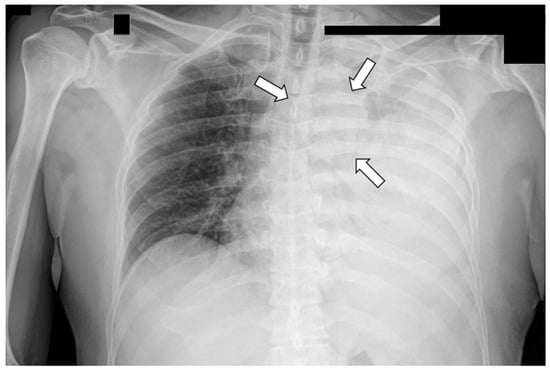

- Aroshidze, B.; Boyapati, L.; Pokhrel, A.; Gotlieb, V.; Khan, A.; Erdinc, B.; Cheema, M.A. Yolk Sac Tumor in the Anterior Mediastinum Presenting as Acute Pericarditis. Am. J. Case Rep. 2022, 23, e932616. [Google Scholar] [CrossRef]